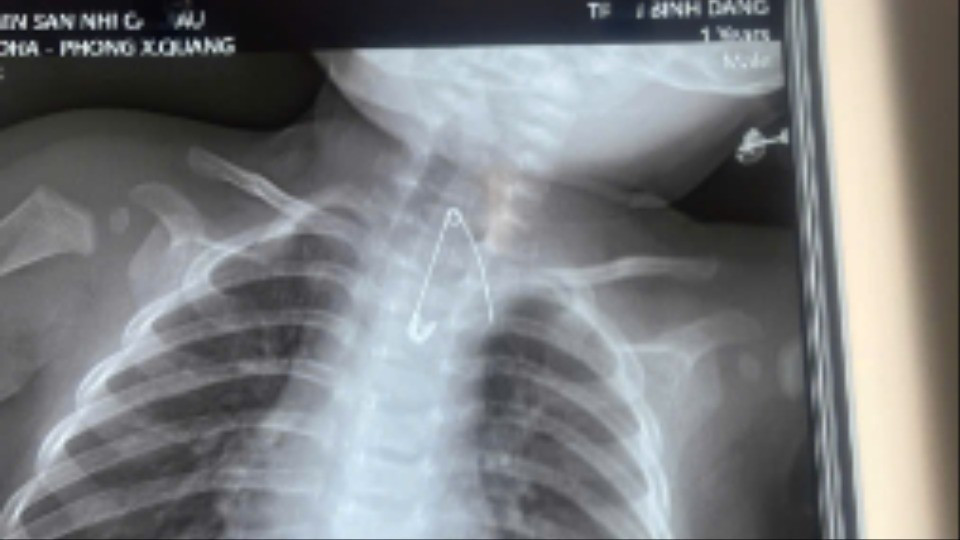

Kim băng nằm sát động mạch chủ bé Đ.

Người nhà cho biết, gia đình có thói quen dùng kim tây (kim băng) ghim bùa bình an vào áo của bé. Qua thăm khám lâm sàng và thực hiện các xét nghiệm cận lâm sàng, các bác sĩ phát hiện một dị vật là kim tây nằm trong mô mềm, ở vị trí sát động mạch chủ, rất nguy hiểm.

Bệnh nhi sau đó được ê-kíp phẫu thuật lấy thành công kim băng, ngăn ngừa các biến chứng nghiêm trọng có thể xảy ra.